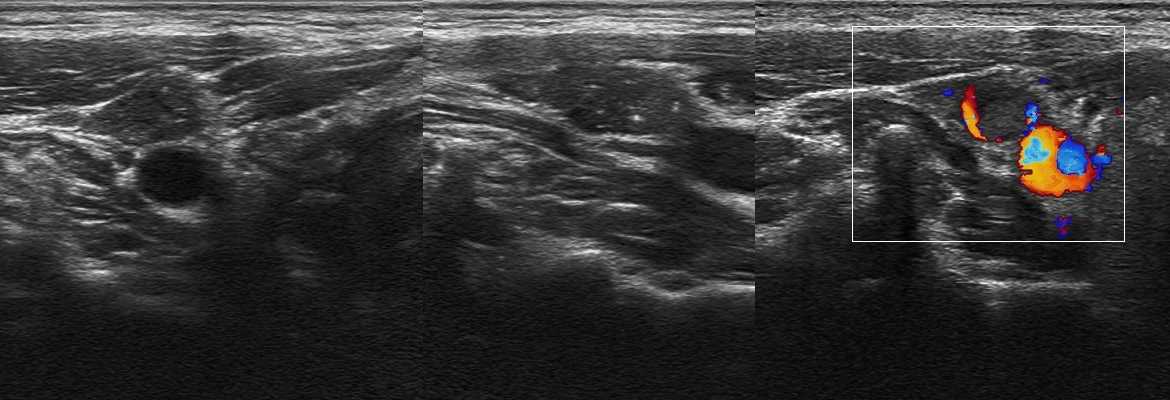

Рисунок. На УЗИ лимфоузел с метастазами папиллярного рака щитовидной железы: эхоструктура неоднородная — мелкие анэхогенные полости и микрокальцинаты; центральный рубчик не определяется; видно подкапсульный кровоток.

Рисунок. На УЗИ группа увеличенных округлых лимфоузлов на шее: гипоэхогенные, неоднородные за счет мелких и крупных анэхогенных, аваскулярных зон — очаги некроза. Заключение по результатам биопсии: Лимфоузлы с метастазами аденокарциномы. Первичную опухоль найти не удалось.

Рисунок. На УЗИ метастазы аденокарциномы легких разрушили нормальную архитектуру лимфоузла: неоднородный за счет чередования гипер- и гипоэхогенных участков, центральный рубчик отсутствует, форма лимфоузла неопределенная, контур нечеткий, что указывает на инфильтративный рост в окружающие ткани.

Рисунок. На УЗИ лимфома (1,2) между углом нижней челюсти и подчелюстной слюнной железой, также лимфоузел (3) с метастазами.